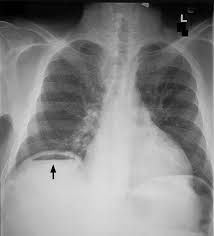

Management of pneumoperitoneum depends on the underlying etiology and the patient's condition. Treatment can include supportive observation, antibiotics, or emergent surgery with repair of luminal defect.